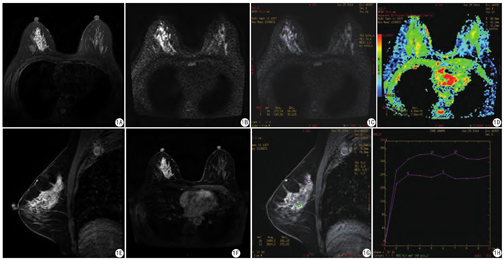

本研究83例炎性病变中在T2WI/IDEAL WATER序列上表现为等信号31例(31/83,37.3%)或稍高信号31例(31/83,37.3%),另见高信号21例(21/83,25.3%);DWI序列上表现为稍高信号33例(33/83, 39.8%)或高信号46例(46/83,55.4%),另见等信号4例(4/83,4.8%)(图1,图2)。

TIC类型以平台型为主,共52例(52/83,62.7%);流入型17例(17/83,20.5%)和流出型14例(14/83,16.9%)。肿块组与非肿块强化组的TIC类型详见表4。

本研究中,非哺乳期乳腺炎性病变的T2WI/IDEAL WATER和DWI信号强度无明显特征性,ADC值的范围较大(0.55~2.15)×10-3 mm2/s,平均值为(1.15±0.30)× 10-3 mm2/s。笔者认为,炎性病变的ADC值波动较大,主要与炎症反应的不同时期、脓肿内容物成分的不同相关。由于乳腺炎性病变内部成分较为混杂,ROI选取的成分不一导致ADC值变化较大。13例伴有脓肿形成病变的ROI选取DWI高信号的中心部位,主要考虑到相对于肿瘤的坏死区一般位于病变边缘,脓肿的坏死区多位于病变中心位置。本组数据可见,炎性病变的ADC值参考价值有限,可重复性较差,不能作为鉴别诊断的主要手段。

本组数据中,非哺乳期乳腺炎性病变的TIC类型以平台型为主(62.7%),与部分文献的描述不尽相同。王丽君等[6]报道,TIC曲线为流出型者多于流入型。谭红娜等[9]报道,58例乳腺炎中98.3%的TIC曲线呈流入型或平台型,可提示良性病变的诊断。在乳腺炎性病变中,不同病灶的TIC类型不同,即使同一病灶,不同区域的TIC类型也有所不同,病灶的TIC类型可能与其处于炎性反应的不同时期有关[10]。当病变处于炎性反应急性期,如脓肿形成,病灶周围新生肉芽组织内含大量新生毛细血管,血管扩张,渗透性较高,TIC可表现为流出型;然而在一些慢性炎性病变中,血管较成熟,渗透性较低,TIC可表现为流入型或平台型[6]。